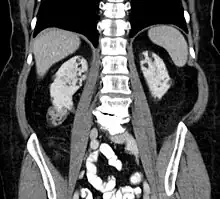

Kidneys

Between 60 and 80% of people with tuberous sclerosis have benign tumors (once thought hamartomatous, but now considered true neoplasms) of the kidneys called angiomyolipomas frequently causing hematuria. These tumors are composed of vascular (angio–), smooth muscle (–myo–), and fat (–lip-) tissue. Although benign, an angiomyolipoma larger than 4 cm is at risk for a potentially catastrophic hemorrhage either spontaneously or with minimal trauma. Angiomyolipomas are found in about one in 300 people without TSC. However, those are usually solitary, whereas in TSC they are commonly multiple and bilateral.

About 20-30% of people with TSC have renal cysts, causing few problems. However, 2% may also have autosomal dominant polycystic kidney disease.

Very rare (< 1%) problems include renal cell carcinoma and oncocytomas (benign adenomatous hamartoma).